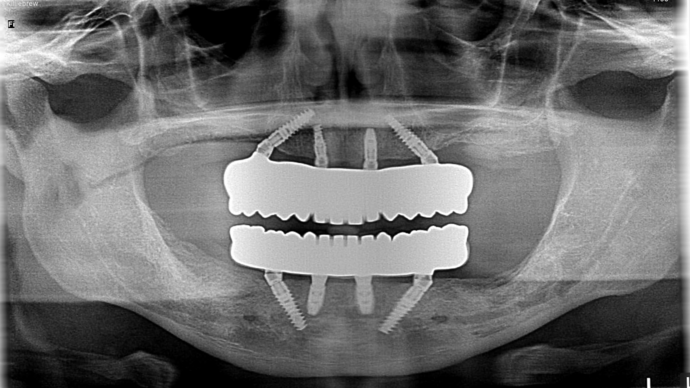

This busy business executive from NY suffered from chronic gum disease (periodontitis) due to genetics and unknown factors and had been to multiple dentists over the years and was tired of getting deep cleanings and still end up with several loose teeth in the mouth with massive bony destruction. As a young busy professional, he researched on getting the most scientific and durable treatment which could be done without several years in treatment and found Dr Bidra online. Dr. Bidra was able to successfully accomplish all his treatment goals by extracting all his teeth and installing Upper and Lower All on 4 implant bridges in 1 day. Most importantly, Dr Bidra did not need to perform any bone grafting procedures to accomplish this treatment.

Procedures : extractions, new implants, All on 4 , All on X, Teeth in a day, no bone grafting and full mouth reconstruction with monolithic zirconia bridges.